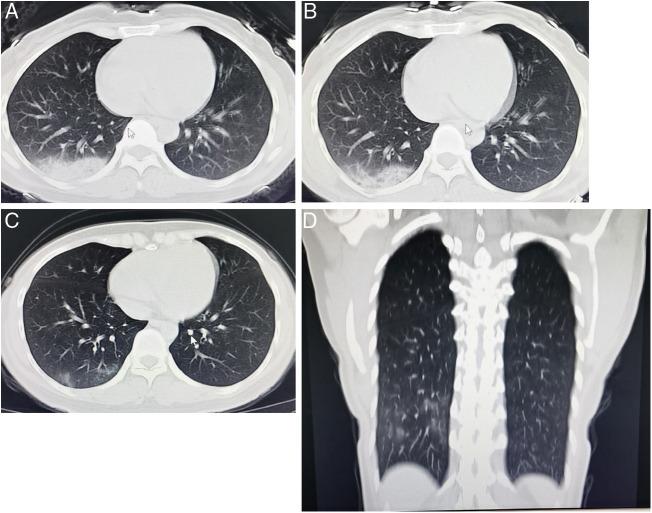

Pre- and post-treatment chest CT changes in a patient with COVID-19.